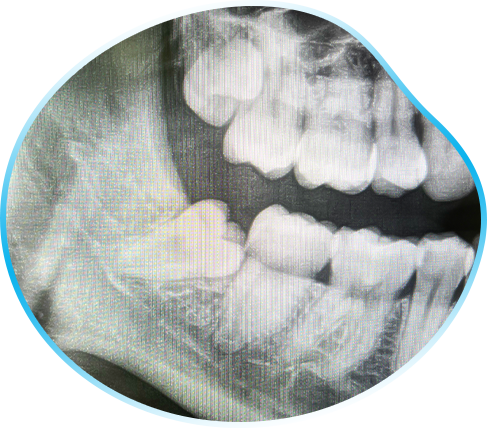

乳歯のむし歯は、黒ではなく白であることが多くあります。

乳歯のむし歯は白い

白いむし歯は黒いむし歯に比べて進行も速いため、知らないうちにむし歯が進行していることがあります。

あっという間に神経まで到達してしまうこともあるので注意が必要です。 -

乳歯のむし歯は歯の間にできやすい傾向があります。特に奥歯は磨き残しが多いため、仕上げ磨きを行い異変がないかをチェックしてあげてください。

歯の間

また、乳歯のむし歯は急に穴があいてしまうことがあります。

歯の間をデンタルフロスでケアしてみて、引っ掛かりがある場合はむし歯の可能性があります。 -